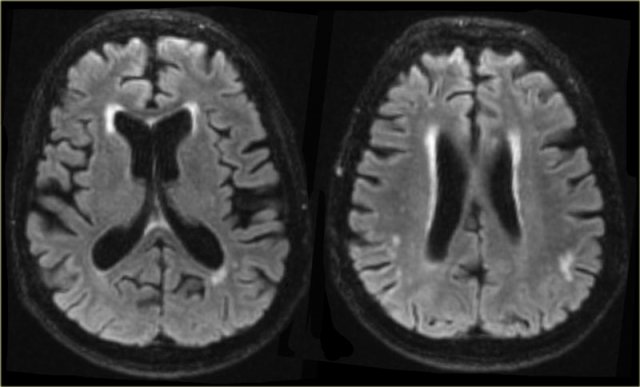

Huntington Disease

Huntington disease is a hereditary neurodegenerative disease (autosomal dominant trait, but often de novo mutations), and can present with early onset dementia as well as choreoathetosis and psychosis.

Imaging shows characteristic atrophy of the caudate nucleus and subsequent enlargement of the frontal horns of the lateral ventricles.